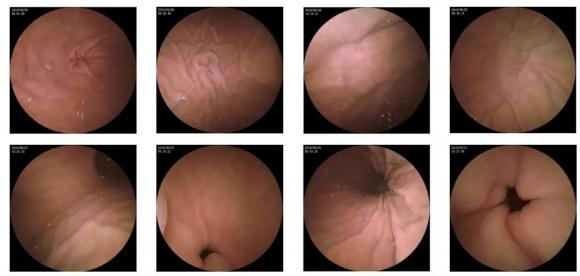

10—15分鐘即可完成賁門、胃底、胃體、胃角、胃竇、幽門等解剖部位觀察,讓胃部檢查更高效。更為重要的是,檢查全程無痛、無創、無麻醉,避免了傳統插管胃鏡帶來的生理痛苦。

膠囊機器人的專利三鏡片鏡頭,可深入觀察0.04毫米微小單位,每秒可拍高達4張高清醫學照片。

任何細微的胃部病變,如胃潰瘍、胃出血、息肉等都無所遁形,盡在大圣磁控膠囊式內窺鏡系統的掌握之中。